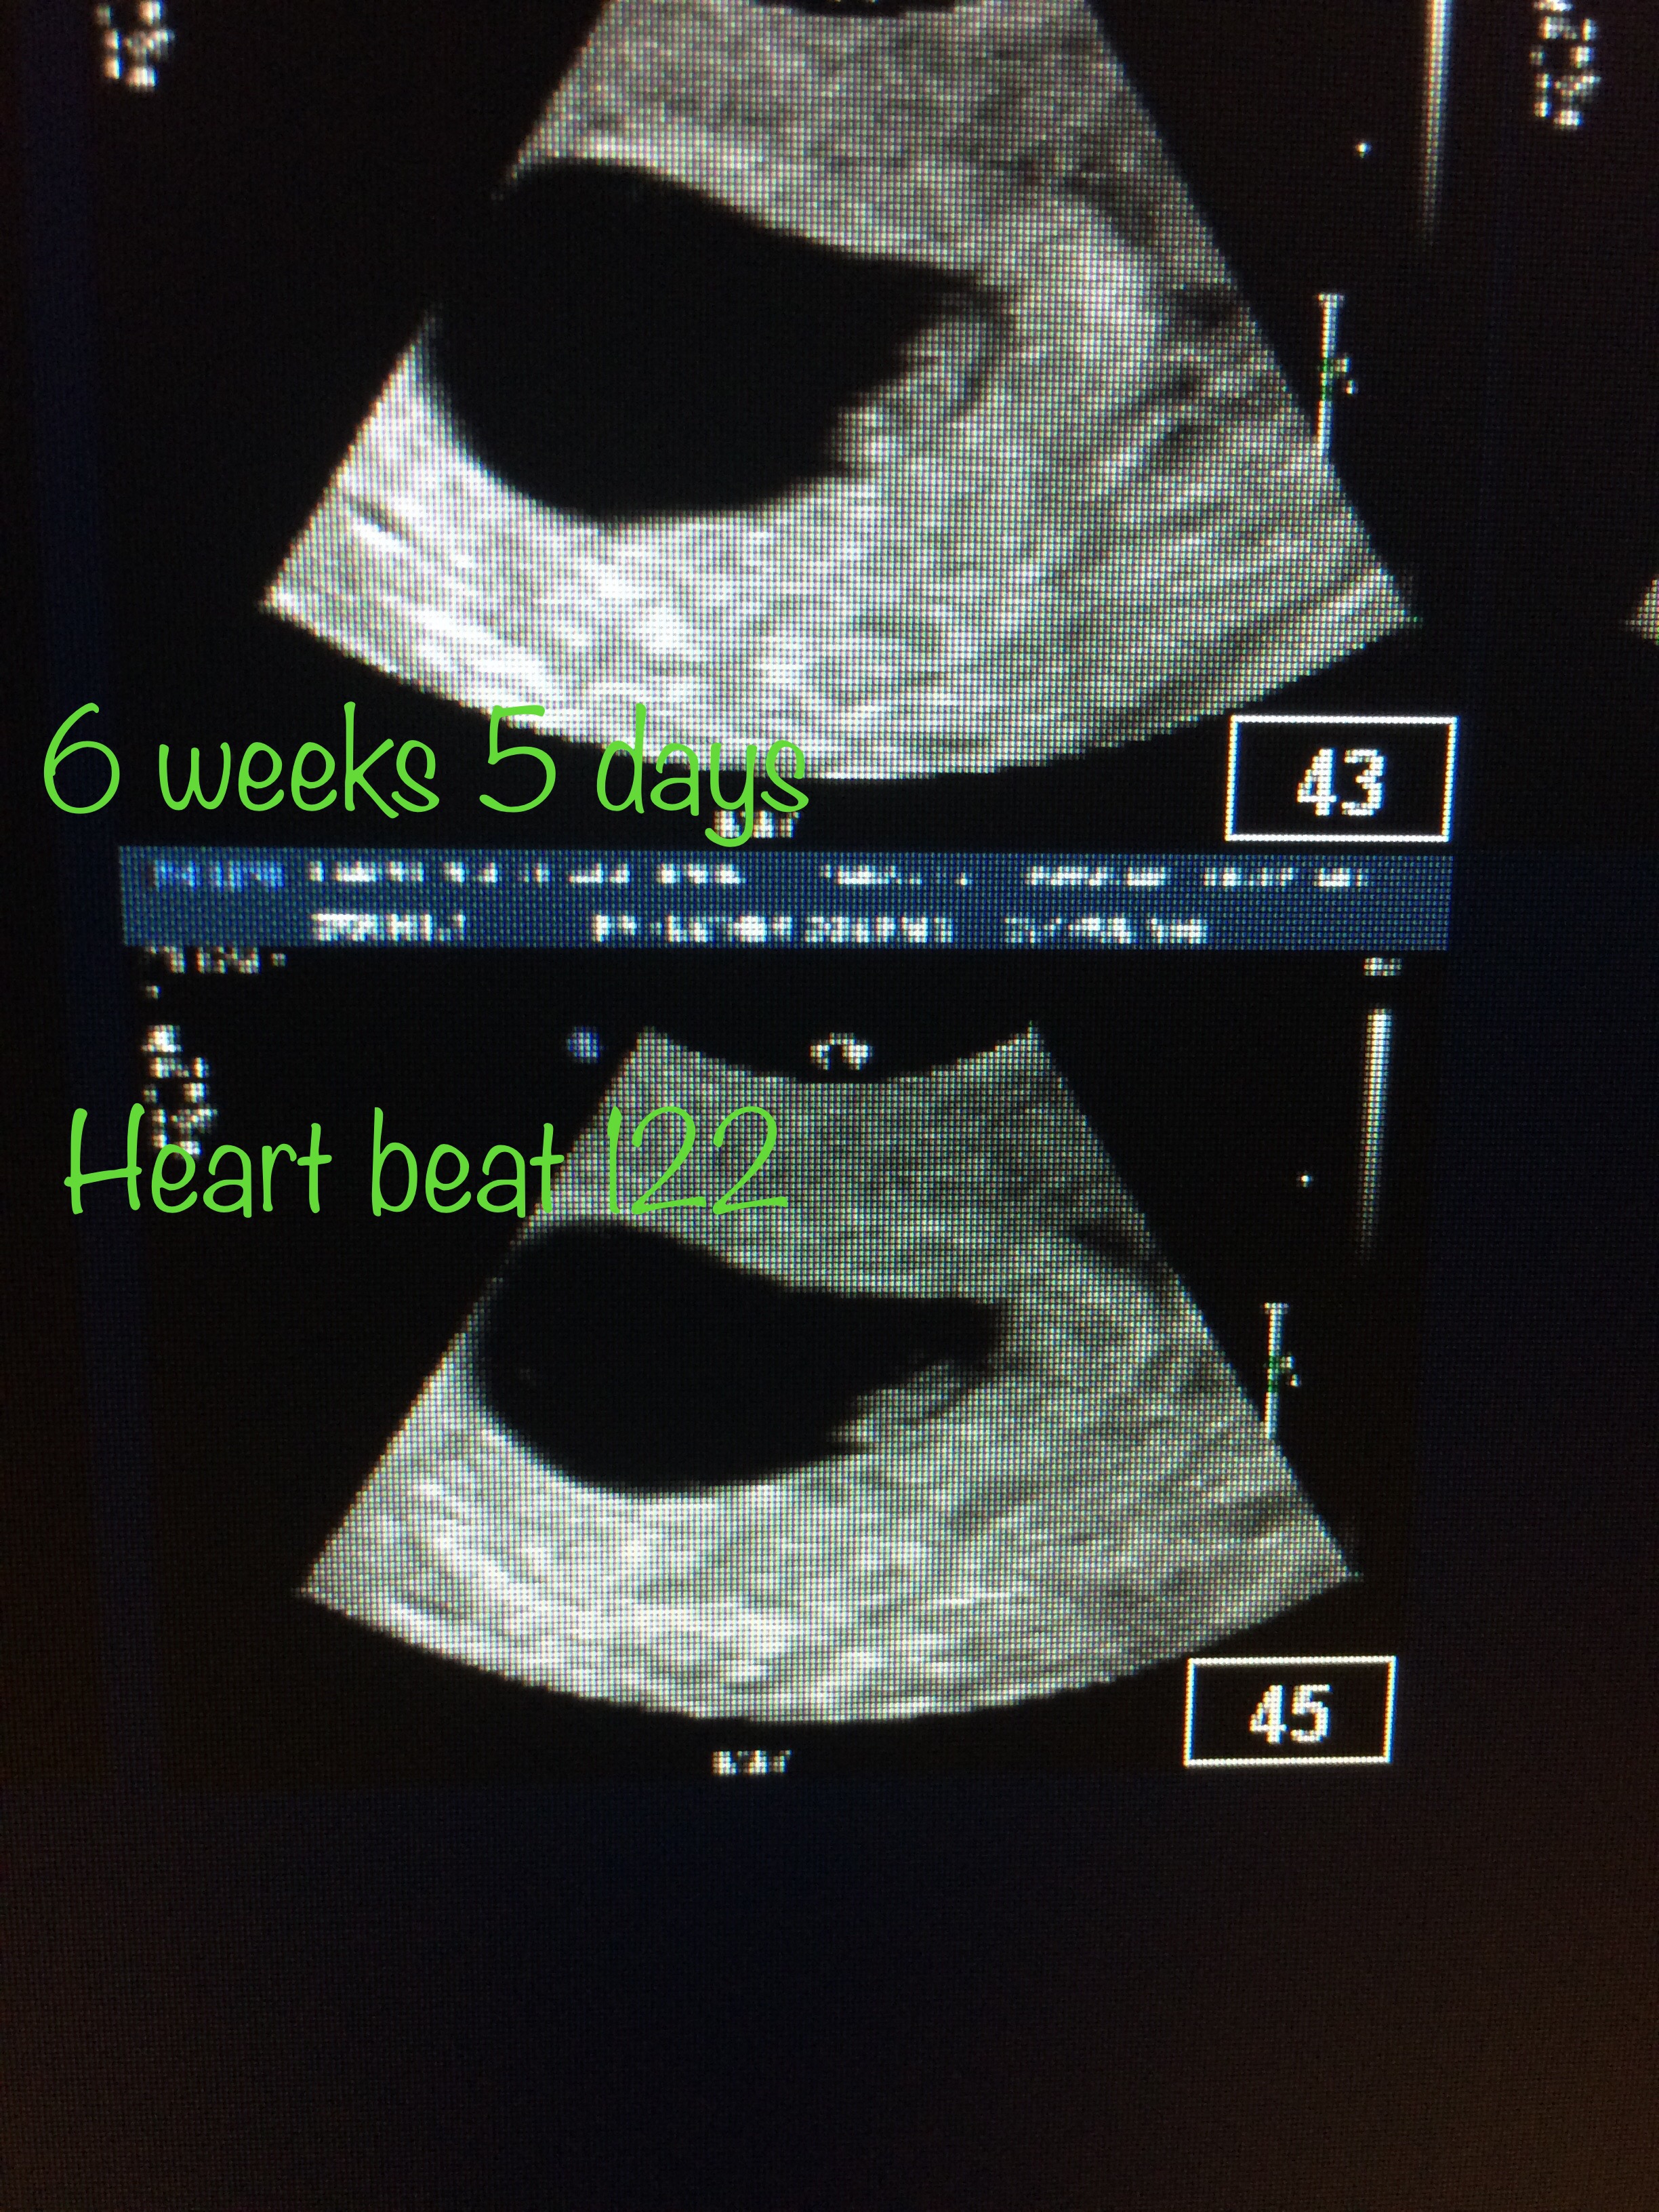

Beginning of March, I take two positive pregnancy tests. Call my OB/GYN because I was concerned that perhaps these were false positives; hormones still floating around in my body from the first pregnancy perhaps? I had three blood tests to see if the HCG hormone levels were rising properly. They were. I had an ultrasound at what was guessed to be 5.5 weeks. Couldn’t see much, but the tech did capture a video clip that showed a little blip of some kind. Came back the following week and the tech could confirm that YES, an embryo and fetal pole had developed. We saw a heart beat. This was all new to us, since we never saw this the first pregnancy.

I was an anxious mess the following weeks, as we had to wait until after Easter holidays for the First Trimester Screen test. This was the test where we found out the sad news in January. Even though we saw the heartbeat at 6.5 weeks, and even though I was gaining some weight and having other pregnancy symptoms…I still didn’t believe this was real. We drove to Calgary on April 24th for the appointment. Once the ultrasound wand hit my belly BOOM-Baby. Baby moving around. Stretching out. Fist pumping. Yawning. There was a baby!

I measured at 13 weeks 5 days, and baby was about 6.4 cm long. While some of our close family and friends knew what was happening (and various others who I couldn’t keep my mouth shut around) we had not made it public knowledge yet. While I wanted to go home and announce it that very night, we waited until the following day.